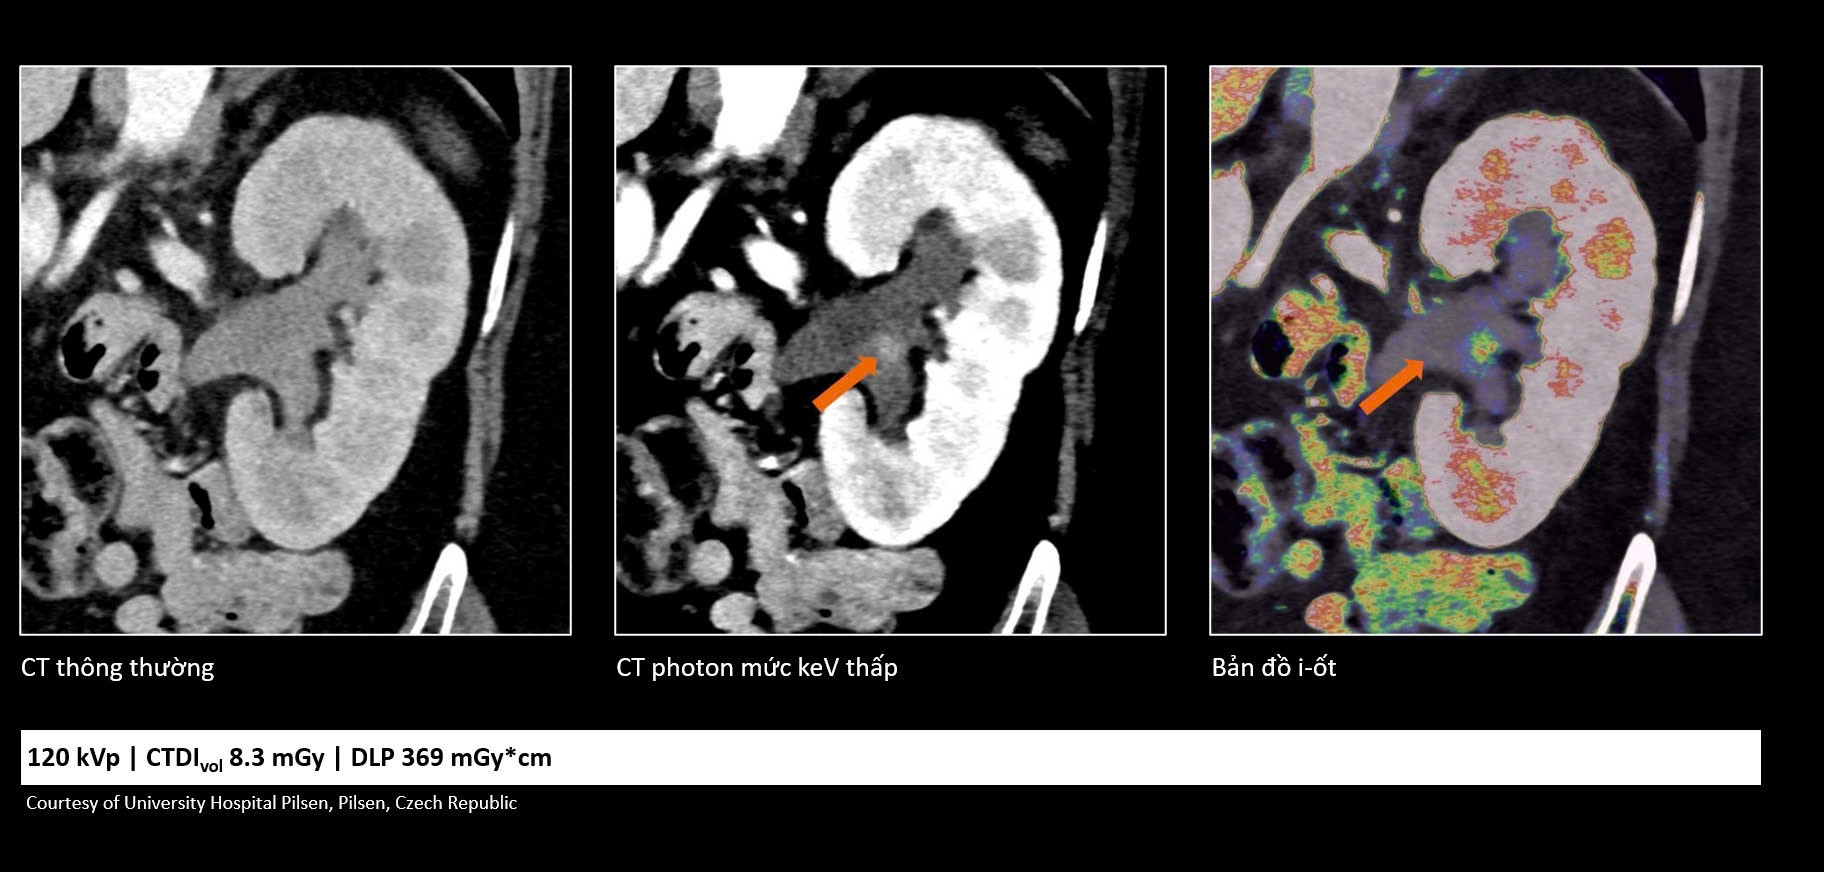

Khác với các hệ thống CT truyền thống, công nghệ cắt lớp vi tính lượng tử mang đến một cách tiếp cận mới. Trước đây, chụp CT chủ yếu giúp phát hiện các thay đổi về hình thái như kích thước, hình dạng hoặc cấu trúc của tổn thương. Với công nghệ mới, nhờ khả năng ghi nhận trực tiếp các photon tia X đi qua cơ thể, hệ thống có thể cung cấp thêm nhiều thông tin hơn về đặc điểm của tổn thương trên hình ảnh.

Những thông tin này không chỉ giúp bác sĩ đánh giá hình thái mà còn cung cấp thêm cơ sở để nhận định sâu hơn về bản chất sinh học của tổn thương, từ đó hiểu rõ hơn tình trạng bệnh ở từng người bệnh và đưa ra các quyết định điều trị phù hợp hơn trong xu hướng y học cá thể hóa và y học chính xác hiện nay.

Trong ung thư, việc phát hiện sớm những tổn thương rất nhỏ đóng vai trò quan trọng trong hiệu quả điều trị. Công nghệ cắt lớp vi tính lượng tử cho phép tái tạo hình ảnh với lát cắt rất mỏng (tới 0,2 mm), giúp phát hiện những bất thường mà trước đây có thể bị bỏ sót. Nhờ đó, bác sĩ có thể nhận diện sớm các dấu hiệu bất thường và đánh giá chính xác hơn đặc tính tổn thương, hỗ trợ hiệu quả trong chẩn đoán sớm cũng như theo dõi tái phát.

Bên cạnh khả năng cải thiện chất lượng hình ảnh, công nghệ cắt lớp vi tính lượng tử còn giúp giảm đáng kể liều tia X và lượng thuốc cản quang sử dụng. Điều này góp phần tăng mức độ an toàn cho người bệnh, đặc biệt với những người có nguy cơ suy thận hoặc mắc bệnh lý nền phức tạp.